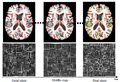

- Project week (Boston, 2010): We have 1) extended HAMMER registration algorithm to work on intensity image, bypassing the pre-segment of MR images; 2) replacing the gaussian propagation with the thin-plate interpolation to achieve more accurate and efficient registration; 3) implement the soft-assignment strategy, instead of the one-to-one correspondence, in detecting correspondence during registration.